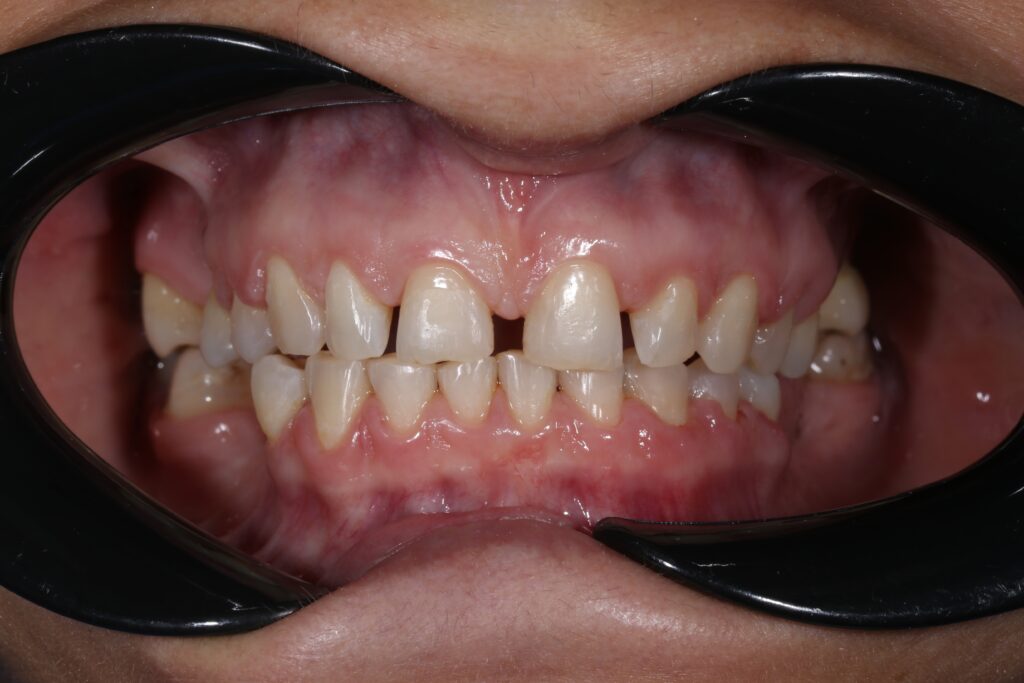

Ситуация до лечения

Пациент обратился за комплексным лечением.

Из-за множественных давних удалений жевательных зубов, произошла деформация зубных рядов, зубы разъехались в область удаленных, что затрудняло протезирование в момент обращения к ортопеду.

Так же можно отметить сильное снижение высоты прикуса (верхние зубы на 100% перекрывали нижние, что вызывало хроническую травму десны), а также повышенную стираемость твердых тканей зубов, что является следствием повышенной нагрузки, которую много лет испытывали передние зубы, в связи с отсутствием жевательных зубов.

В связи со всеми вышеперечисленными факторами, пациентка нуждалась в тотальной реабилитации.